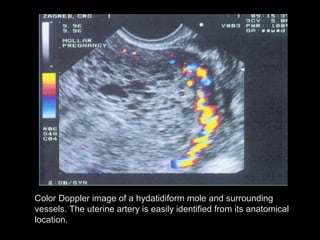

Color Doppler image of a hydatidiform mole and surrounding

vessels. The uterine artery is easily identified from its anatomical

location.

Color Dopplor facilitates visualization of the enlarged spiral

arteriesclose proximity to the “ snow storm” appearance